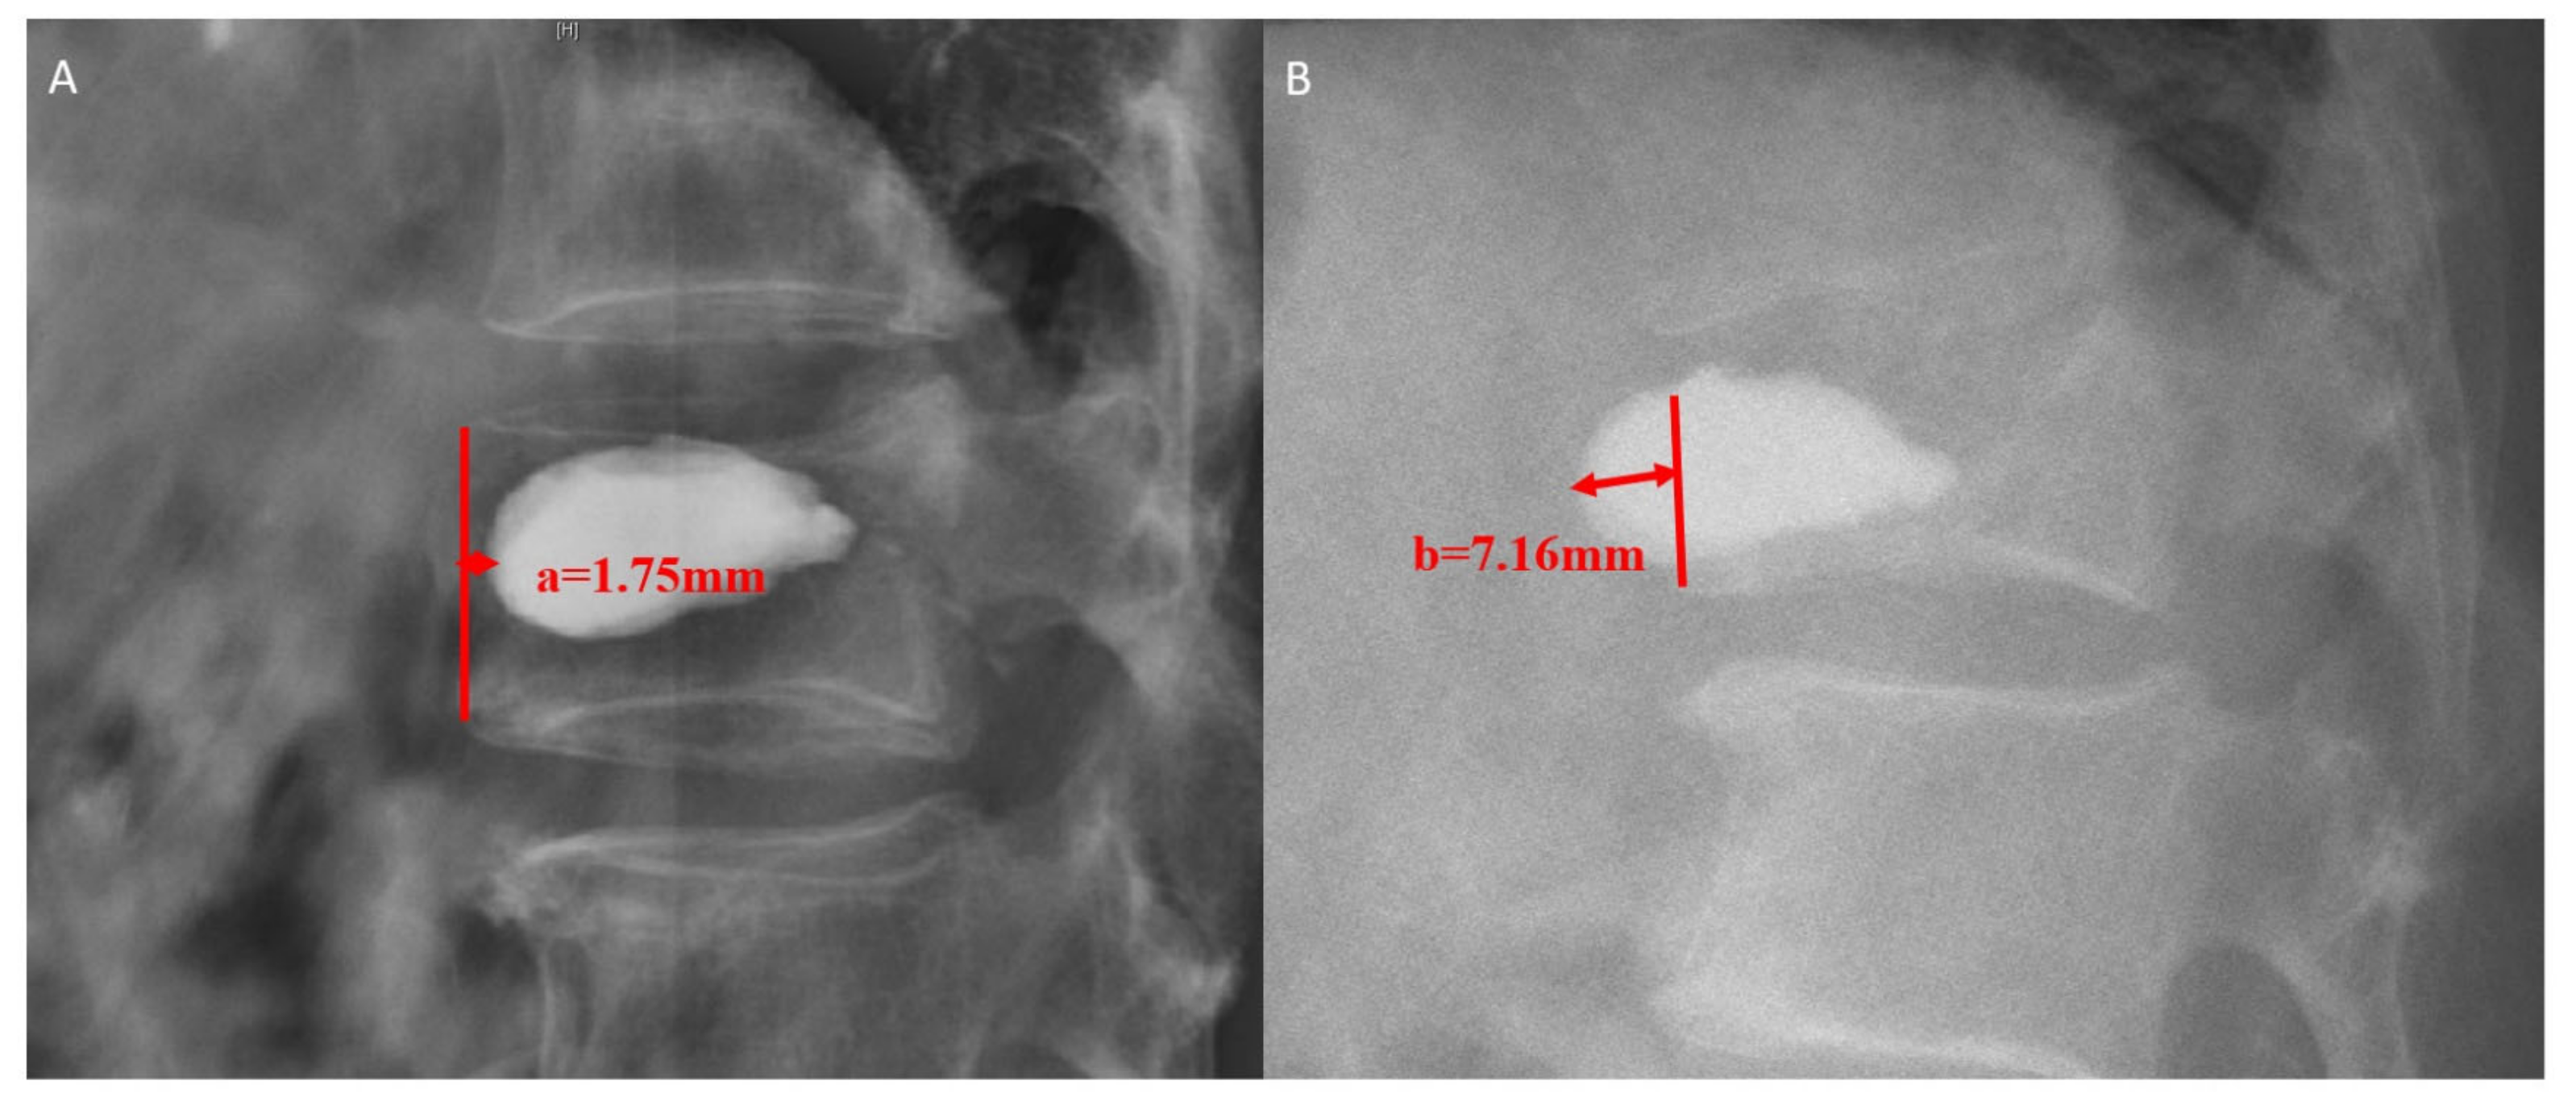

From www.researchgate.net

Plain radiograph of a patient with an L3 compression fracture with the Compression Fracture Calcitonin Calcitonin is another effective medication used for pain management in compression fractures, especially when they. High quality evidence was found supporting the efficacy of salmon calcitonin with reduction in compression fracture pain after 1. Vertebral compression fractures are the most common complication of osteoporosis, with 700,000 cases reported every year in the united states. This review concluded that calcitonin appeared. Compression Fracture Calcitonin.

Preoperative MRI and Xray show a L3 compression fracture with Compression Fracture Calcitonin Calcitonin is another effective medication used for pain management in compression fractures, especially when they. Vertebral compression fractures are the most common complication of osteoporosis, with 700,000 cases reported every year in the united states. High quality evidence was found supporting the efficacy of salmon calcitonin with reduction in compression fracture pain after 1. Osteoporotic vertebral compression fractures (vcfs) are. Compression Fracture Calcitonin.